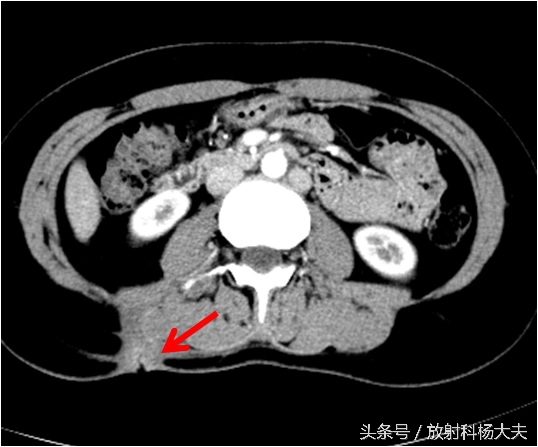

骨科接着开了腰椎CT,骨科大夫怀疑背部是一个窦道,猜测窦道可能是脊柱旁,因此开了腰椎CT平扫,腰椎CT扫描的时候是以腰椎和椎间盘为主的,范围不大,但我们却在不大的范围内发现了问题,除了窦道,肾上有东西!但腰椎CT平扫实在难以评价,因此做了腹部增强CT,发现了实属罕见的情况:那个确实是个窦道,如下图红箭所示,窦道外口在体表,也就是流水的地方。窦道的上口却是在肾脏!

如下图,右肾上长了个东西,囊性的,壁挺厚。